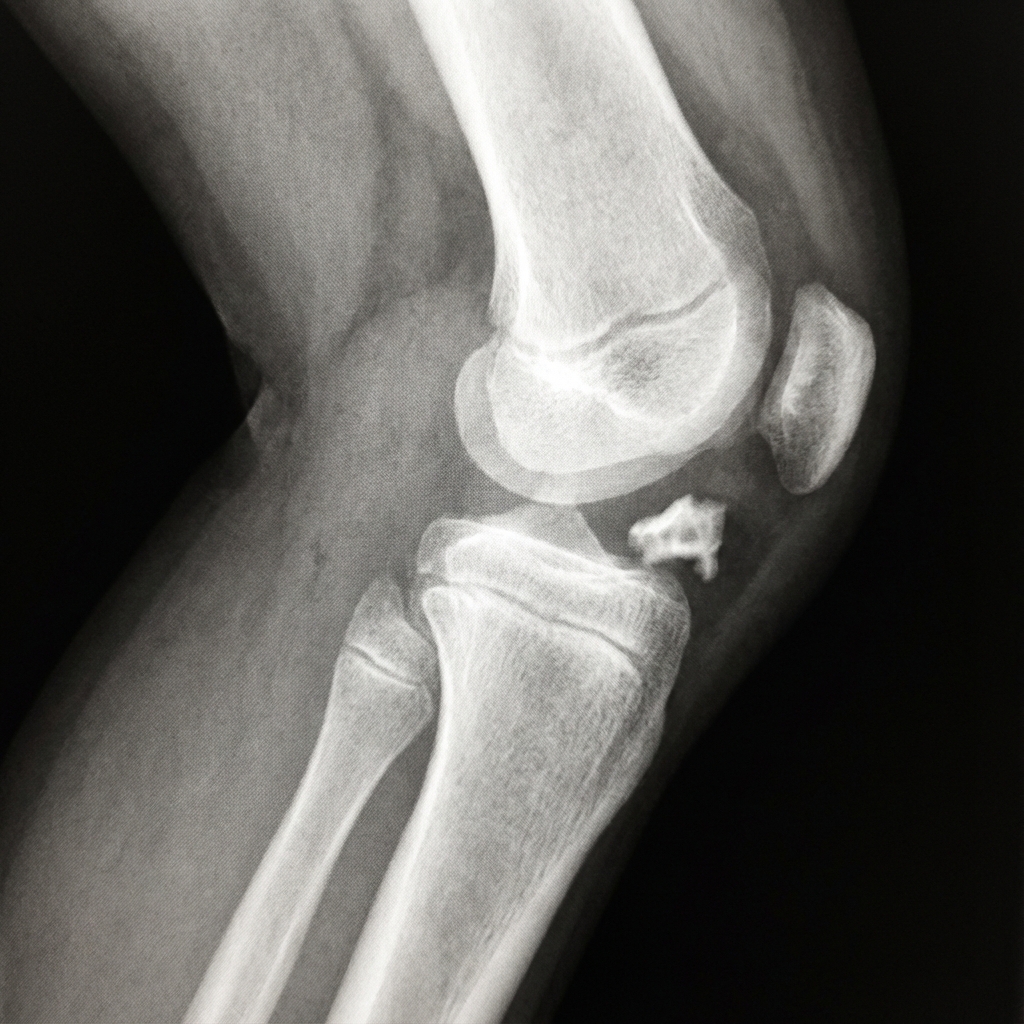

Lateral knee radiograph in a 10-year-old child demonstrating a Meyers and McKeever Type III tibial spine fracture. The anterior tibial eminence fragment is completely displaced and rotated superiorly. There is associated hemarthrosis causing joint effusion. The fragment appears to be sitting above the level of the tibial plateau. This degree of displacement requires arthroscopic or open reduction with internal fixation.